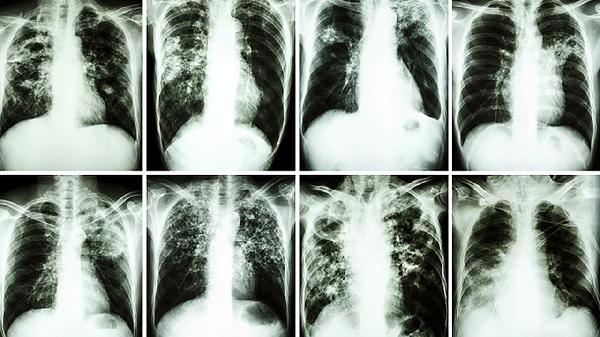

肺磨玻璃結節(jié)是指肺部影像學檢查中出現(xiàn)的邊界模糊、密度均勻增高的類圓形陰影,可能由炎癥、出血、纖維化或早期肺癌等引起。

肺磨玻璃結節(jié)在胸部CT上表現(xiàn)為云霧狀淡薄影,其病理基礎多為肺泡壁增厚或肺泡腔內部分充填。這類結節(jié)可分為純磨玻璃結節(jié)和混合性磨玻璃結節(jié)兩種類型。純磨玻璃結節(jié)通常密度均勻,可能對應非典型腺瘤樣增生或原位腺癌等良性或低度惡性病變?;旌闲阅ゲAЫY節(jié)包含實性成分,惡性概率相對較高,可能為微浸潤性腺癌或浸潤性腺癌。結節(jié)的大小、形態(tài)、邊緣特征及隨訪變化是判斷良惡性的重要依據(jù)。直徑小于5毫米的結節(jié)多為良性,超過8毫米的結節(jié)需密切監(jiān)測。部分結節(jié)可能由肺部感染、間質性肺炎、肺出血或局灶性纖維化等非腫瘤性因素導致。

對于持續(xù)存在的肺磨玻璃結節(jié),尤其是伴有分葉、毛刺、胸膜牽拉等惡性征象時,需警惕肺癌可能。長期吸煙史、家族腫瘤史或接觸致癌物質的人群更應重視。臨床處理需結合結節(jié)特征與患者個體情況,采取定期復查、抗炎治療后復查或穿刺活檢等策略。部分高度懷疑惡性的結節(jié)可能需手術切除以明確診斷。隨訪過程中結節(jié)增大或實性成分增加通常提示需要積極干預。